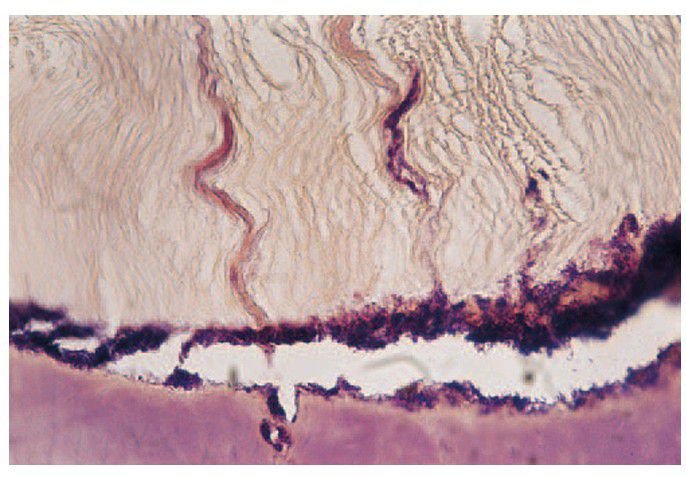

Caries spread along the amelodentinal junction at higher power showing how enamel is undermined and invaded from below. The terminations of the dentinal tubules are also infected but destruction, at this stage, is mainly at the expense of the enamel because of its higher mineral content.